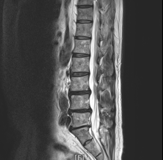

整形外科にて脊柱管脊柱管狭窄症と診断され、腰に3回注射するも効果なし。

発赤、腫脹、熱感、萎縮、側弯なし、疼痛回避姿勢あり、腰椎前弯減少

L4/L5/S1間の右椎間関節に圧痛と放散痛

腰椎軽度後弯、右起立筋・右殿筋ややスパズム

脊椎全体フィクセーション(特に腰椎伸展、胸腰移行部、上部頸椎)